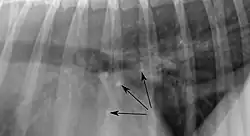

Pulmonale Osteome sind etwa 2 mm große, klar abgrenzbare, mineralisierte Knoten in der Lunge älterer Hunde. Die Anzahl und Verteilung sind variabel. Pulmonale Osteome haben keinen Krankheitswert und gelten als Zufallsbefund. Aufgrund ihrer großen Röntgendichte sind sie deutlich erkennbar. Von anderen herdförmigen Veränderungen der Lunge, wie Tumoren, lassen sie sich meist schon aufgrund ihrer geringen Größe abgrenzen, da diese in der Regel mindestens 5 mm groß sein müssen, um im Röntgen-Thorax erkannt zu werden.